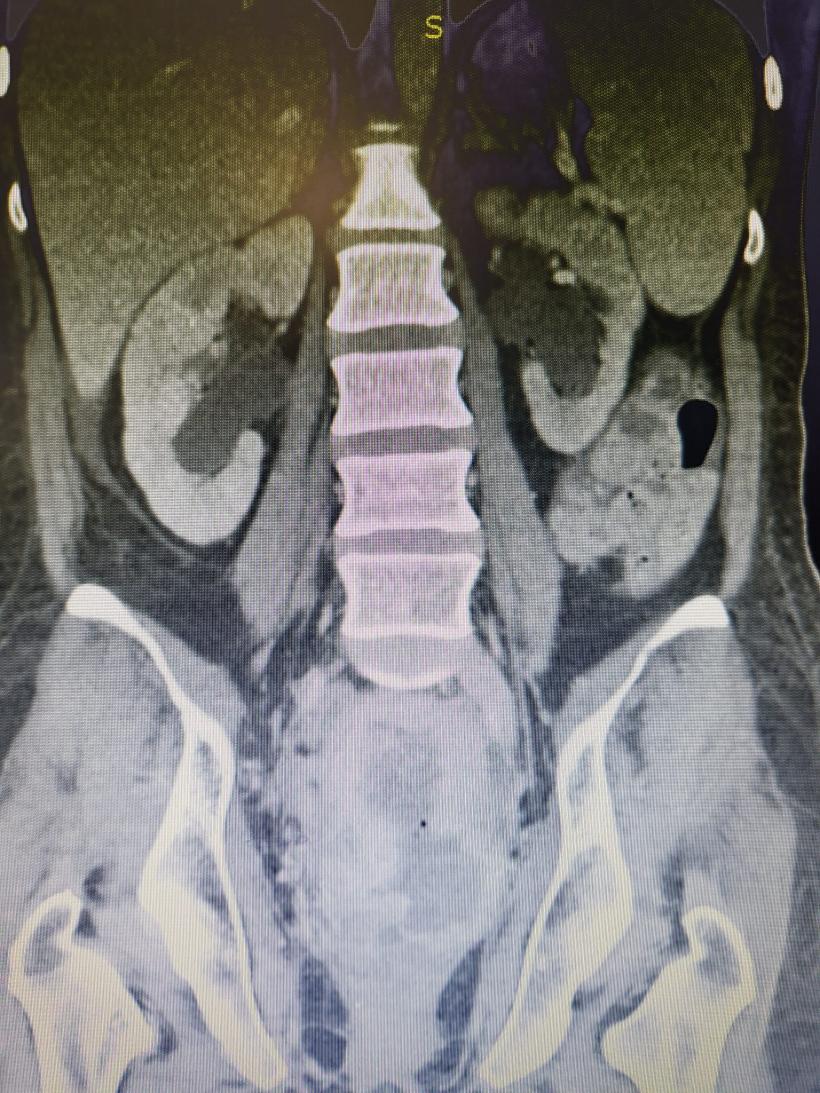

Tânără de 37 de ani trimisă să moară, salvată de medicii din Brașov: De cele mai multe ori imposibilul e posibil! | Galerie Foto | Imagine 2

Facebook Bogdan Moldovan